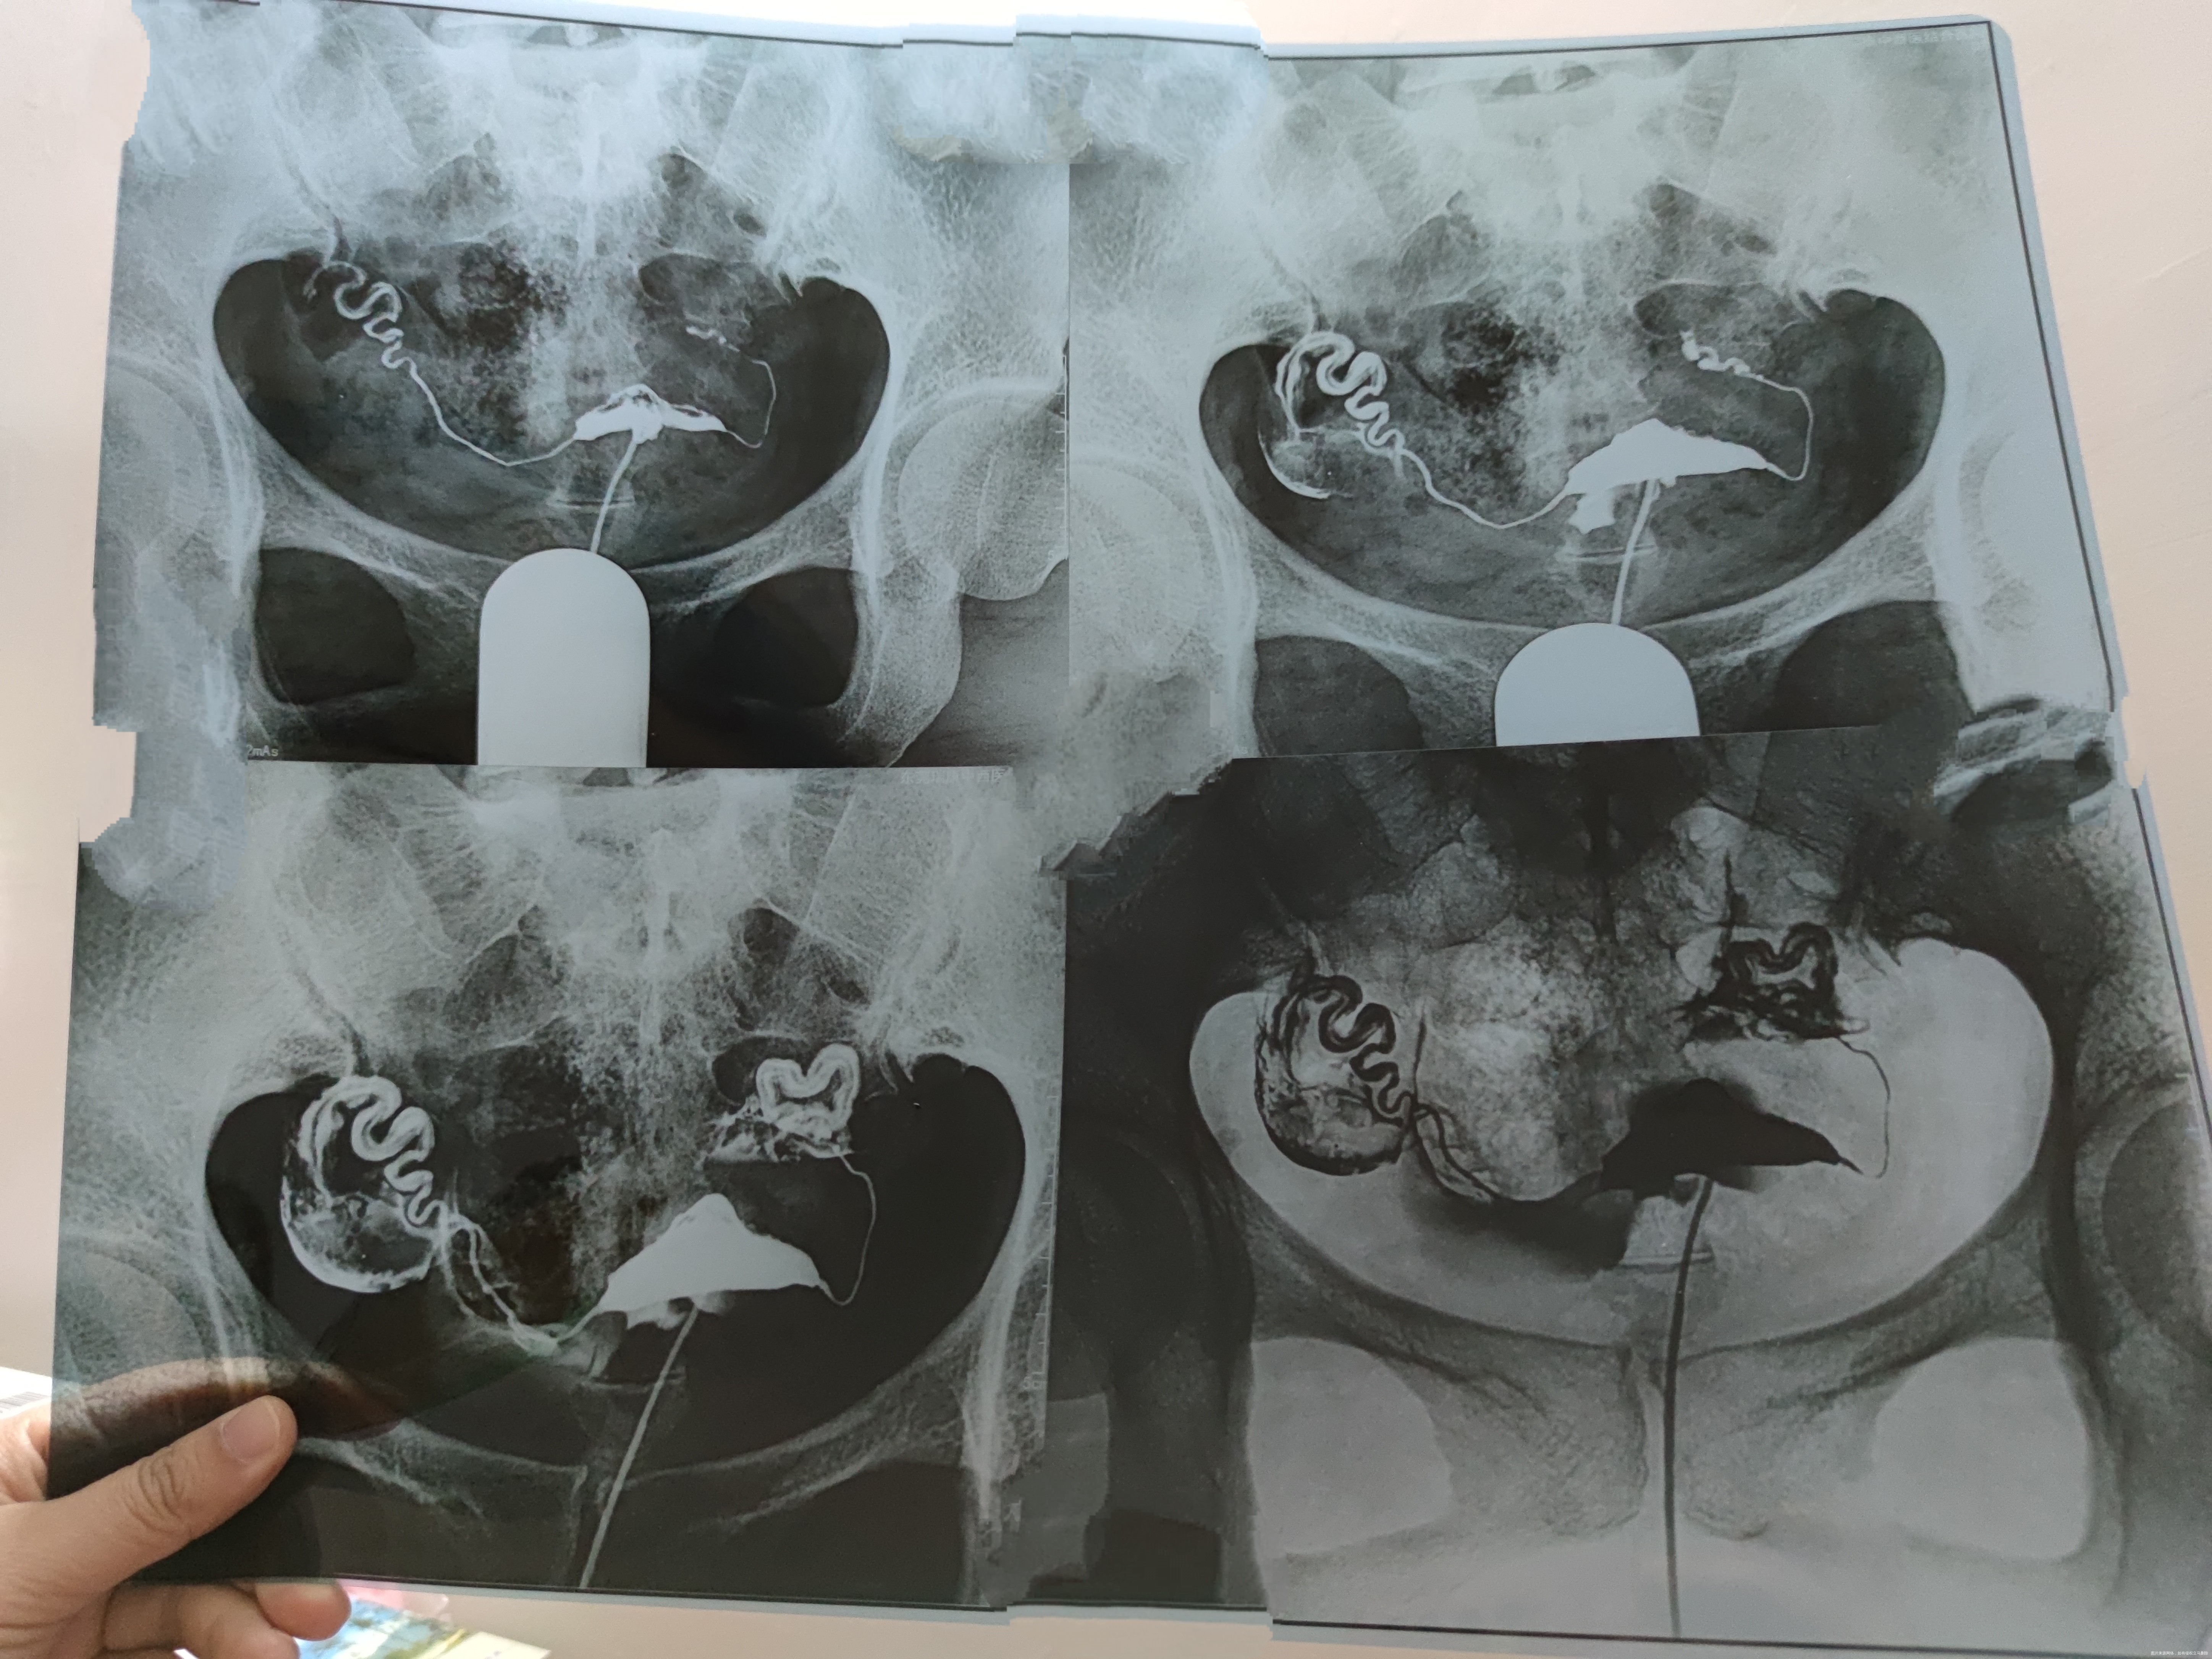

双侧输卵管上举,左侧输卵管远端迂曲,盆腔造影剂弥散量少,局限,属于双侧输卵管周围粘连,通而不畅,内分泌正常。